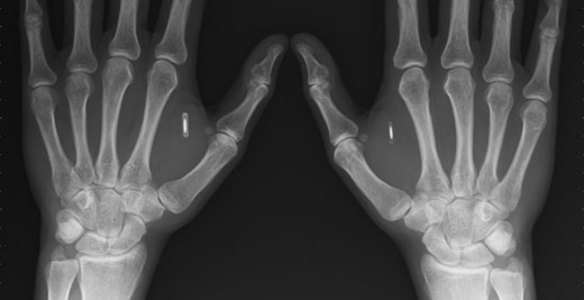

Имплантация чипа (RFID chip hand implantation) Теперь, когда чипизация стала реальностью, сможем ли мы и наши дети использовать свободу слова и свободу выбора, будем ли мы действительно защищены от терроризма, или все же поверим, что это очередная игра политических фигляров и не будем полуроботами под тотальным контролем? Решать только нам самим, пока у нас окончательно не отобрали возможность самостоятельного выбора.